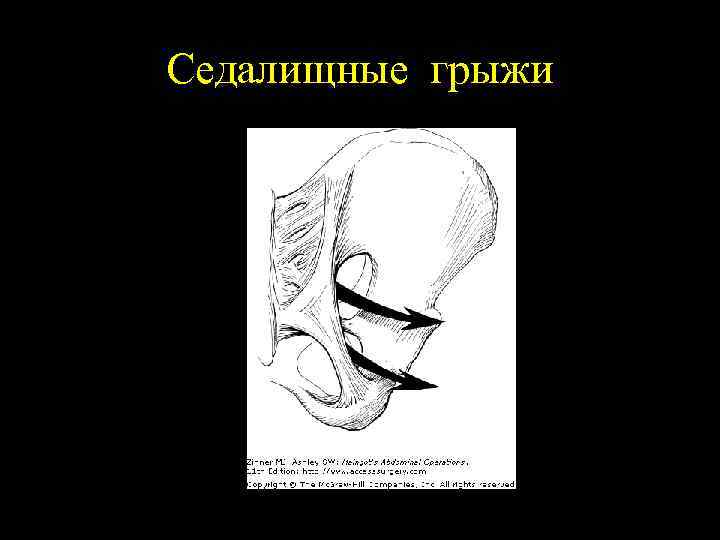

Седалищные грыжи